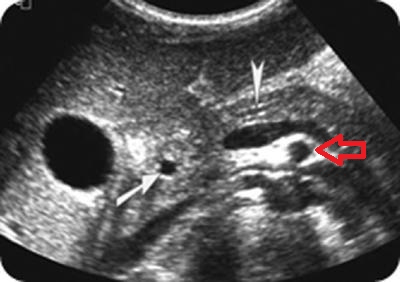

What is the red arrow pointing at?

SMA